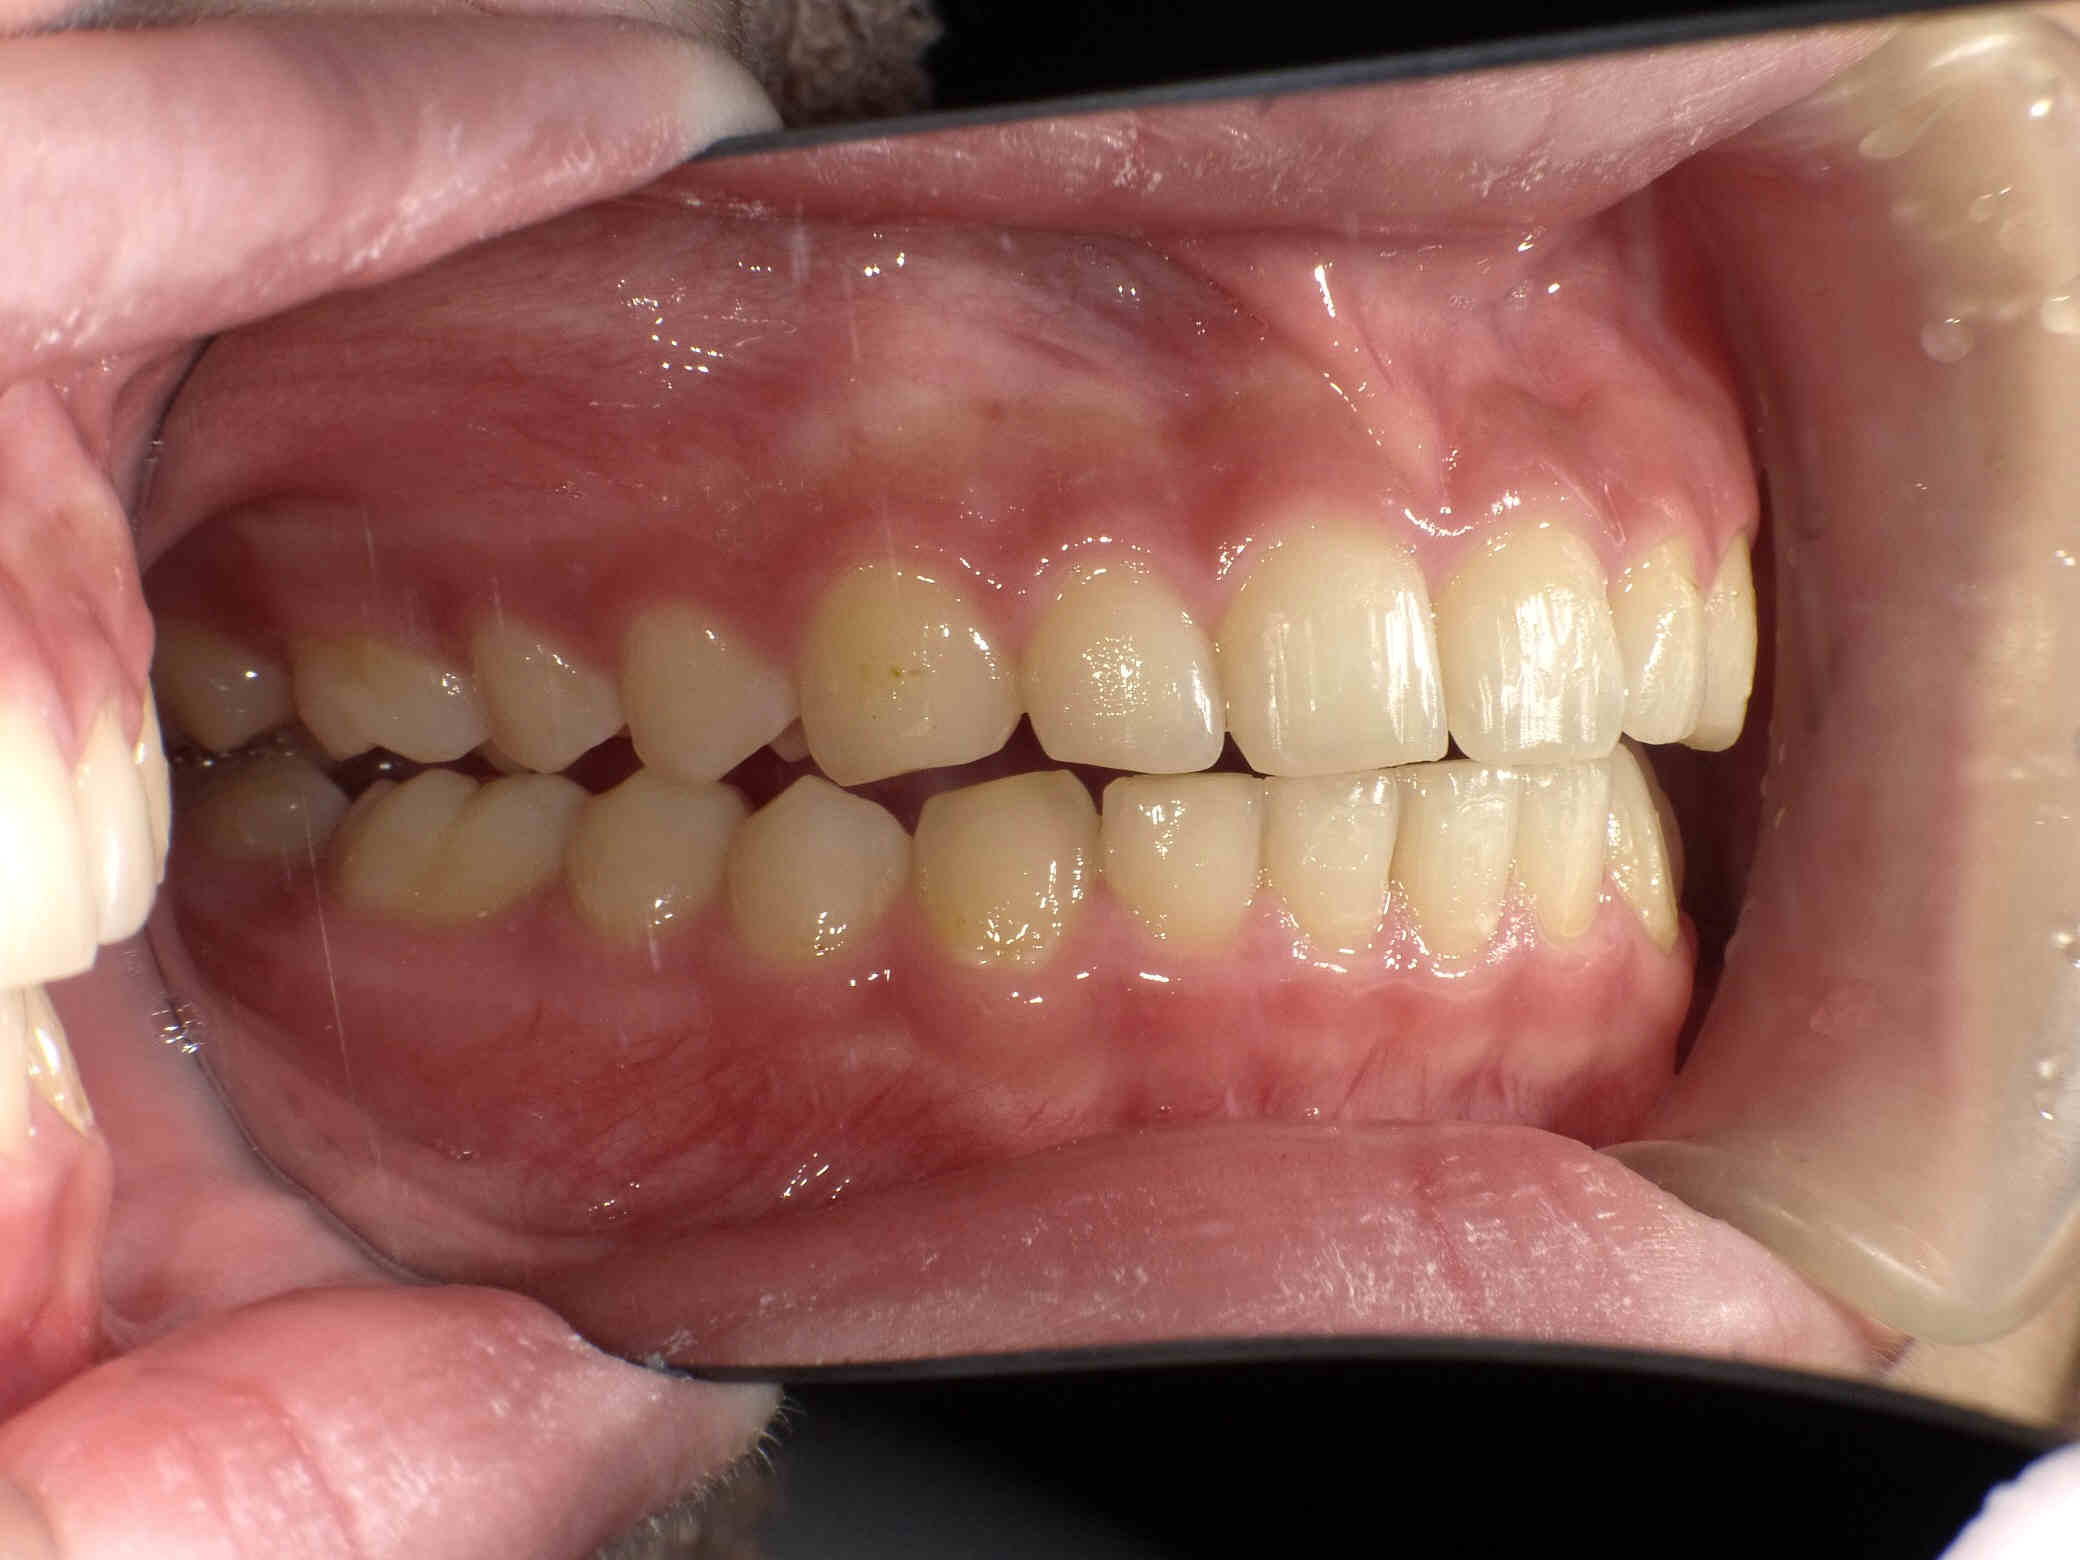

12歳6ヶ月〜スタートです。

やや出っ歯傾向で、噛み合わせが深く

歯並びがデコボコな鋏上咬合(はさみじょうこうごう)という状況でした。

上下の歯がすれ違っている状態で、一部の歯に過度の負担がかかってしまいます。

今回はご希望のワイヤー矯正で治療を行い、スタートから1年半で美しい歯並びに改善しました。